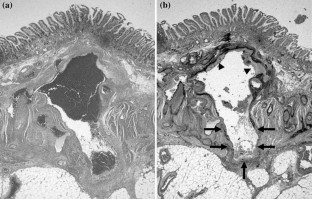

This report presents the case of a patient with Cowden syndrome who had arteriovenous malformations (AVMs) at the jejunum and the ileum and experienced intestinal bleeding. A 54-year-old Japanese male presented with general fatigue and melena. Endoscopic examinations showed gastrointestinal polyposis from the esophagus to the rectum. However, the site of bleeding was not identified. There were some papules on his face and neck. He also had macrocephaly and had multiple papillomas along the gum-line. These findings indicated a clinical diagnosis of Cowden syndrome. Enhanced computed tomography (CT) and angiography analyses indicated the presence of AVMs at the jejunum and the ileum. He was treated with partial resection of the jejunum and ileum including these two AVMs. This was a rare case of two AVMs involving the small bowel in a patient with Cowden syndrome. Enhanced CT was very useful and convenient for the detection of gastrointestinal AVMs in this case.

Fig. 3